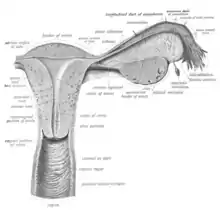

When not sexually aroused, the vagina is a collapsed tube, with the front and back walls placed together. The lateral walls, especially their middle area, are relatively more rigid. Because of this, the collapsed vagina has an H-shaped cross section.[10][14] Behind, the upper vagina is separated from the rectum by the recto-uterine pouch, the middle vagina by loose connective tissue, and the lower vagina by the perineal body.[15] Where the vaginal lumen surrounds the cervix of the uterus, it is divided into four continuous regions (vaginal fornices); these are the anterior, posterior, right lateral, and left lateral fornices.[9][10] The posterior fornix is deeper than the anterior fornix.[10]

Supporting the vagina are its upper, middle, and lower third muscles and ligaments. The upper third are the levator ani muscles, and the transcervical, pubocervical, and sacrocervical ligaments.[9][16] It is supported by the upper portions of the cardinal ligaments and the parametrium.[17] The middle third of the vagina involves the urogenital diaphragm.[9] It is supported by the levator ani muscles and the lower portion of the cardinal ligaments.[17] The lower third is supported by the perineal body,[9][18] or the urogenital and pelvic diaphragms.[19] The lower third may also be described as being supported by the perineal body and the pubovaginal part of the levator ani muscle.[16]